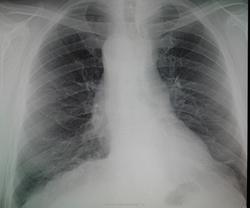

Зачем с барием? Видно же, что она справа.

Да, остается неясность, я бы скопически покрутил.

Она трахею влево оттесняет, значит сама справа находится. Нет неясности.

Прошу прощения, можно спросить - как Вы объяснили тень, наводящую сомнение на Коллегу?..

Бок, если верно поставлен, выполнен правый. Аорту праволежащую он выявить помог нам. Но тень, наводящую сомнение на Наталью Ивановну не проявил. И Ленивец отъявленный, верно, про левый бок говорила.) В общем, тень осталась для части коллег не объяснима.)